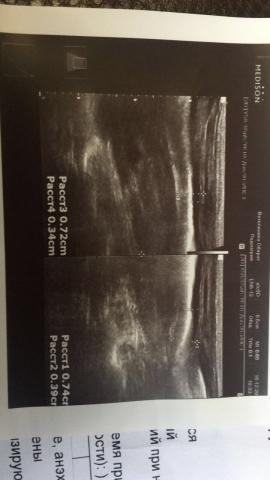

Если можно, то немного подробнее. На основании чего вам поставили такой диагноз, только на основании проведенного УЗИ? Может быть, собаке брали какие-то анализы? Если да, то выложите, пожалуйста, здесь их результаты. Если только данные УЗИ, то это разговор ни о чем (я имею ввиду панкреатит). Гастрит по данным УЗИ вообще не ставят.

Поставили диагноз на основании УЗИ , а до этого сдавали кровь

К сожалению, ничего не могу рассмотреть. Попробуйте сами прочесть описание с фото. Если сможете, сделайте снимок более качественным. Или можно снять крупнее по частям. Может быть, тогда буквы будут видны более четко.

Я думаю, в вашем случае не стоит паниковать. В анализах ничего особенного нет. Небольшие превышения некоторых показателей в пределах допустимого. Не вижу пока ничего, указывающего на озвученные диагнозы.

Спасибо, фотографии четкие. Я все прочитал. Как я и думал, там и "не пахнет" никаким гастродуоденитом, а тем более, панкреатитом.